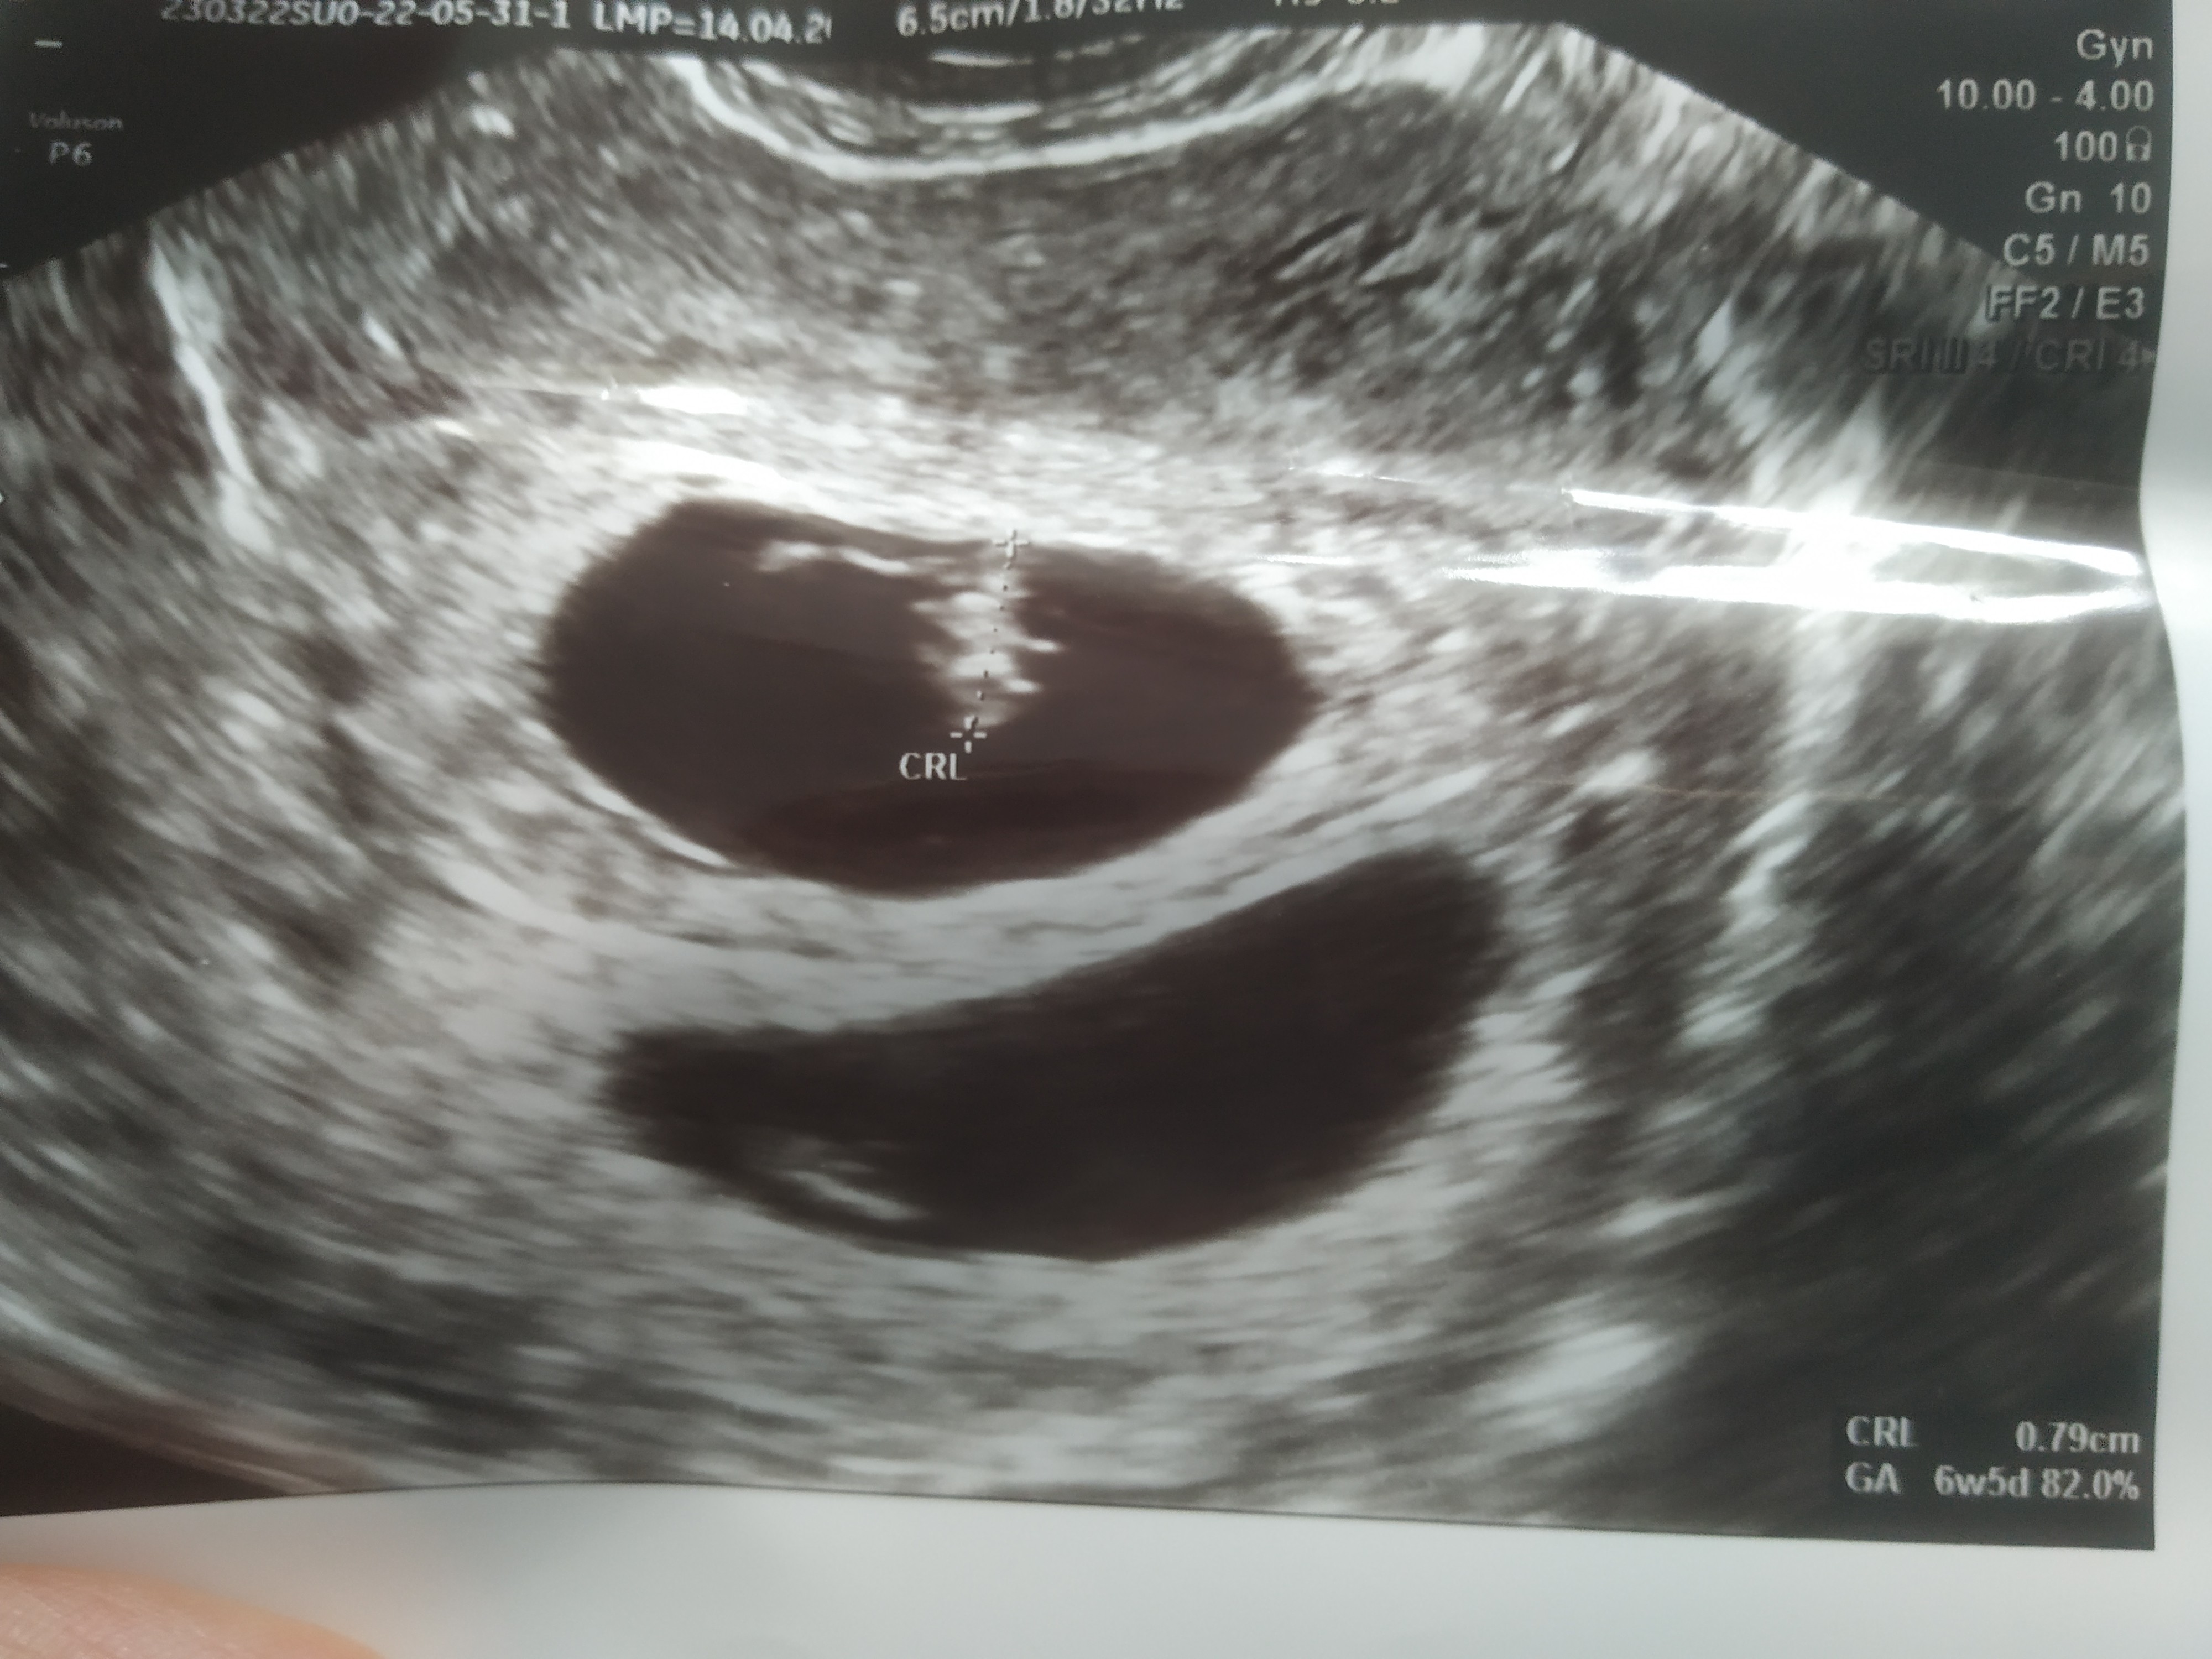

Witam, w piątek byłam u ginekologa który zobaczył 3 pęcherzyki ciążowe.

Wczoraj kolejna wizyta i tylko jeden, w sumie lekarz coś mówił że jest drugi ale mały.

I tu moje pytanie czy ten mały to może być krwiak? Czy jest szansa, że to ciąża bliźniacza? Zobacz załącznik 1421172Zobacz załącznik 1421173